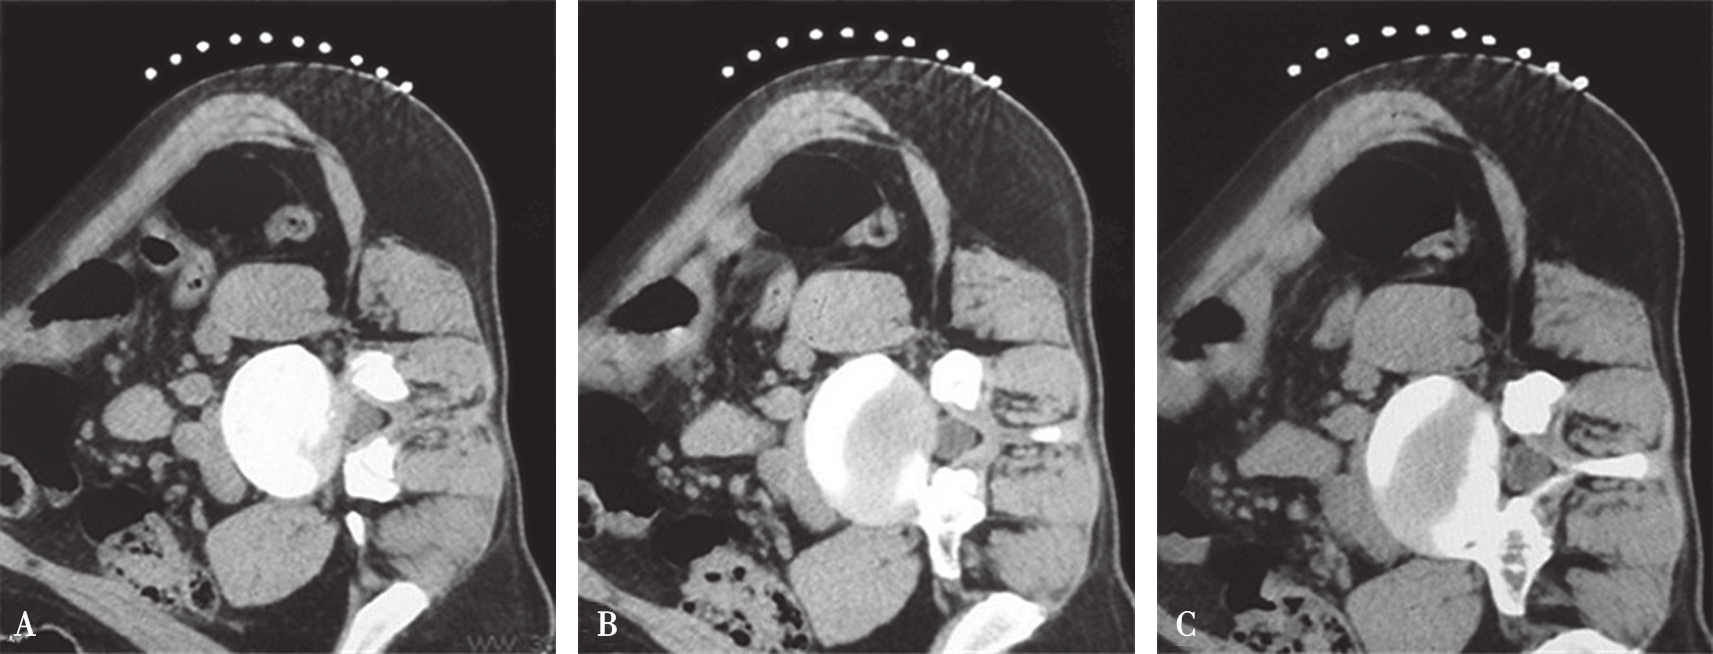

在扫描产生的多层横断面中选择出最符合穿刺要求的一层,作为设计入路和引导穿刺定位的操作平面,我们将该层称为“靶点操作平面”。根据不同的手术目的选择该平面的要求也不同:避骨入路类手术如经椎板间入路椎间盘靶点定位类,应选择具有最大程度避开神经、血管、脏器、骨质而到达靶点的平面,如图3-3-12中显而易见图B是最合适的平面;经椎间隙侧方入路时的扫描图像中(图3-3-13),图B最合适;而经骨入路类手术如经皮椎体骨折复位外固定、椎体成形术等,应选择椎弓根宽大处的平面,如图3-3-14中图B作为操作平面最合适。CT机架角度扫描的横断位平面自然也是倾斜的,而穿刺定位入路是在该平面内的,因此存在如下关系:CT机架扫描角度=靶点操作平面角度=定位针穿刺时的头足倾斜角度(图3-3-15)。

图3-3-12 L 5 /S 1 经椎板间隙入路-不同层面横断位像

A.靶点偏头侧平面;B.靶点操作平面;C.靶点偏足侧平面

图3-3-13 L 4/5 侧方入路-不同层面横断位像

图3-3-14 沿椎弓根轴线扫描的不同层

A.椎弓根偏头侧平面;B.椎弓根中间平面;C.椎弓根偏足侧平面